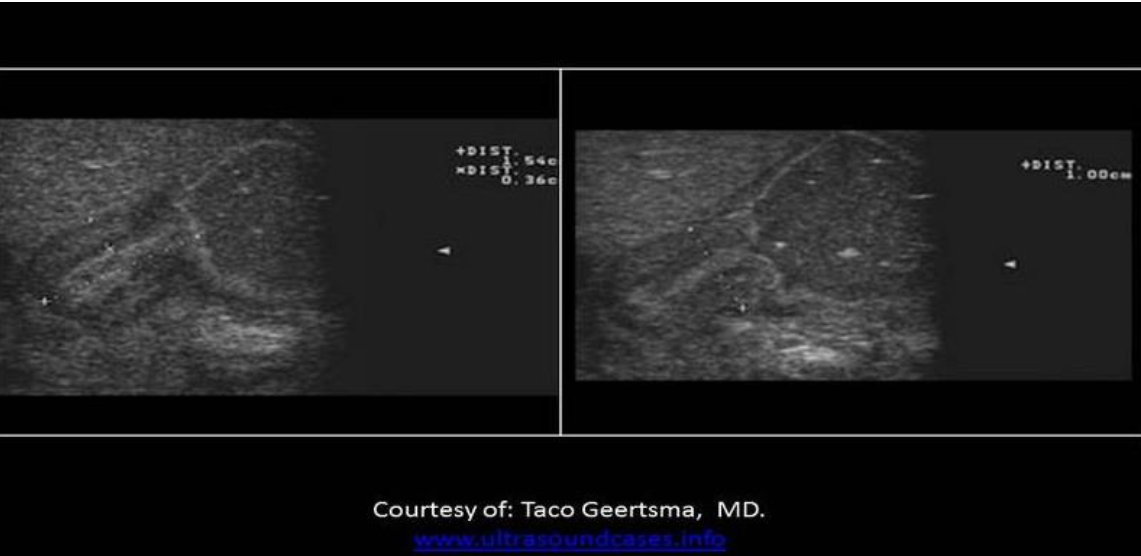

Find the rectus sheath hematoma

Top left is a benign mass with lobulated borders and the top right is a lipoma. Both are located in the subcutaneous tissues/fat between the skin and the anterior rectus sheath. The lipoma has smooth borders and an echogenicity similar to the surrounding fat.

The bottom right image demonstrates a spigelian hernia, between the right rectus abdominis and right oblique muscles.

The bottom left image demonstrates a hematoma in the rectus abdominis muscle, between the anterior and posterior rectus sheaths.

Find the lipoma

The top two images demonstrate solid masses that are superficial to the rectus abdominis muscle. Top left is a benign mass with lobulated borders and the top right is a lipoma. Both are located in the subcutaneous tissues/fat. The lipoma has smooth borders and an echogenicity similar to the surrounding fat.